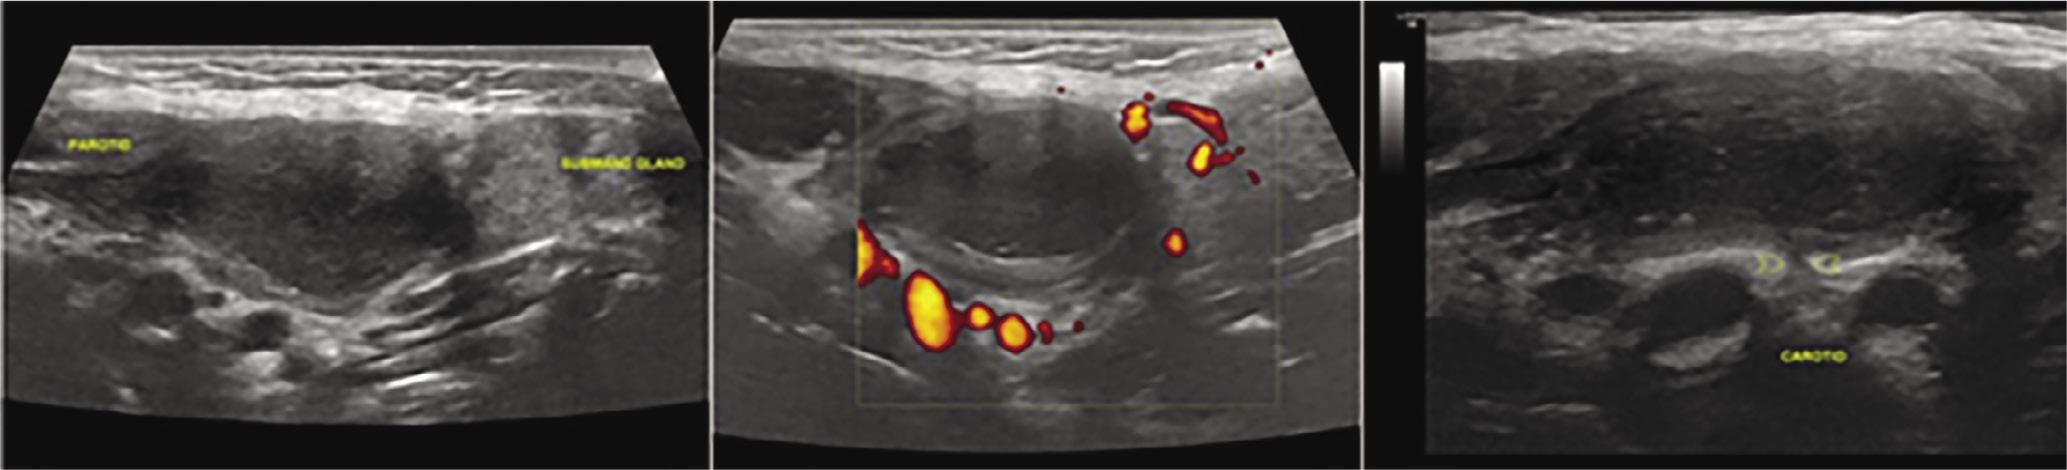

1st cleft cyst: in the inferior pole of the parotid gland one can observe a cystic-like lesion of multilobular borders, septa that are of low vascularity on color Doppler, and thick content, attached to the lateral borders